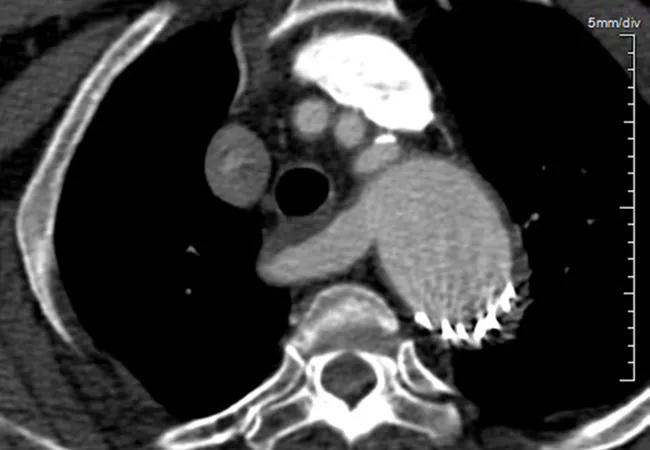

ARSA (depicted in the image above) is a surprisingly common anomaly of the aortic arch, reported in approximately 1% of the general population. It occurs as a result of abnormal entanglement of the aortic anatomy that causes the right subclavian artery to arise from the descending thoracic aorta just distal to the left subclavian artery. Variations in precisely where the aberrant artery ends up passing can result in a variety of clinical presentations.